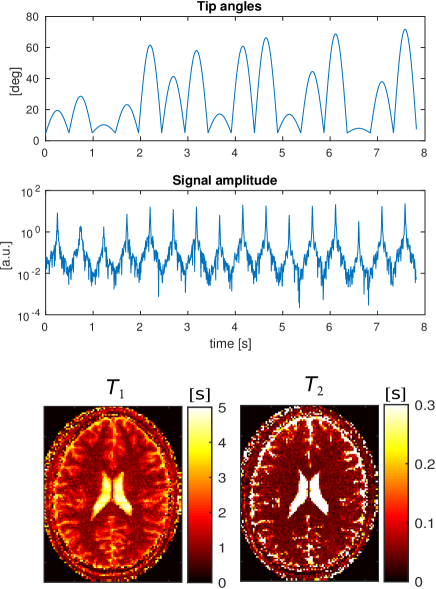

The central slice of a numerical human brain model [20] is used to create a synthetic MR-STAT data set. The reconstructed in-plane resolution is 1mm×1absent1\times 1mm which corresponds to a 216×216216216216\times 216 voxels matrix. The tissue parameters for the biological components are given in Table 2. The amplitude and phase maps of the transmit RF field are obtained from a numerical electromagnetic simulation of a 3T headcoil driven in quadrature. Without loss of generality, a uniform receive sensitivity is assumed in this example. The off-resonance map is taken from [21] and is scaled to fit the range of [15,15]1515[-15,15] Hz in the head (see the bottom of Fig. 7). For the acquisition, a Cartesian trajectory is used. The duration of each read out is 0.86 ms with a 4 μ𝜇\mus dwell time per sample. The read out lines (kysubscript𝑘𝑦k_{y} direction) cover the 2D k𝑘k-space in ascending order, starting with the smallest negative values of kxsubscript𝑘𝑥k_{x} and repeating this pattern for the equivalent of 8 full k𝑘k-space coverages. In total, 172817281728 lines are acquired in 8.3 seconds resulting in approximately 3.71053.7superscript1053.7\cdot 10^{5} time data points. The random tip angles sequence is shown at the top of Fig. 2.

A Gaussian shaped RF pulse and a slice selective gradient waveform along the z𝑧z axis are applied. The RF pulse is 1 ms long and is defined on a 0.10.10.1 ms dwell time step. The slice profile variation throughout the sequence is taken into account by discretizing the spatial domain in the slice-selective direction by 50 points and integrating the magnetization response for each point. This integration is applied to both the forward (signal simulation) and backward (reconstruction) steps. Gaussian noise is superimposed to the time-domain signal such that noise2/signal=0.01subscriptnormnoise2normsignal0.01\|\text{noise}\|_{2}/\|\text{signal}\|=0.01. The resulting time-domain signal is shown at the bottom of Fig. 2.

We employ two different sequences. The first RF train (Fig. 8, top) consists of 16 sinusoidal sweeps. Each lobe corresponds to a k𝑘k-space filling and is randomly scaled to achieve maximum amplitude levels in the range 5oθ75osuperscript5o𝜃superscript75o5^{\mathrm{o}}\leq\theta\leq 75^{\mathrm{o}}.

The spatial resolution is 1.8×1.81.81.81.8\times 1.8 mm2 and the scan time is 7.8 seconds. The measured signals are shown in Figures 8 and 9.

Figure 2: Tip angles and time-domain signal for the MR-STAT sequence applied to the in-silico simulated head experiment at 3T.

Figure 8: In-vivo experimental validation of MR-STAT for a sinusoidal RF train sweep. From top to bottom: the flip angle train, the recorded signal and the reconstructed parameter maps.